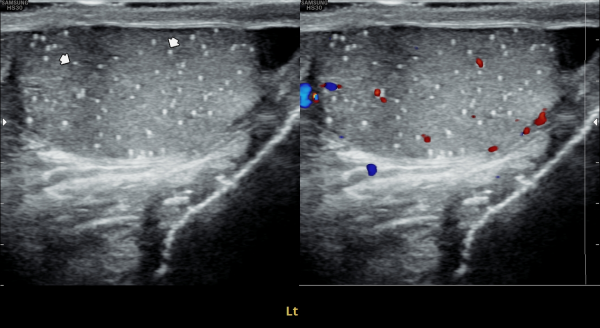

고환의 통증으로 내원한 환자분의 고환의 초음파 검사상 우측 고환의 미석증이 관찰되는 초음파 사진입니다.

Here is an ultrasound image of a patient who presented with testicular pain, showing microlithiasis in the right testis.

고환의 통증으로 내원한 환자분의 고환의 초음파 검사상 좌측 고환의 미석증이 관찰되는 초음파 사진입니다.

Here is an ultrasound image of a patient who presented with testicular pain, showing microlithiasis in the left testis.